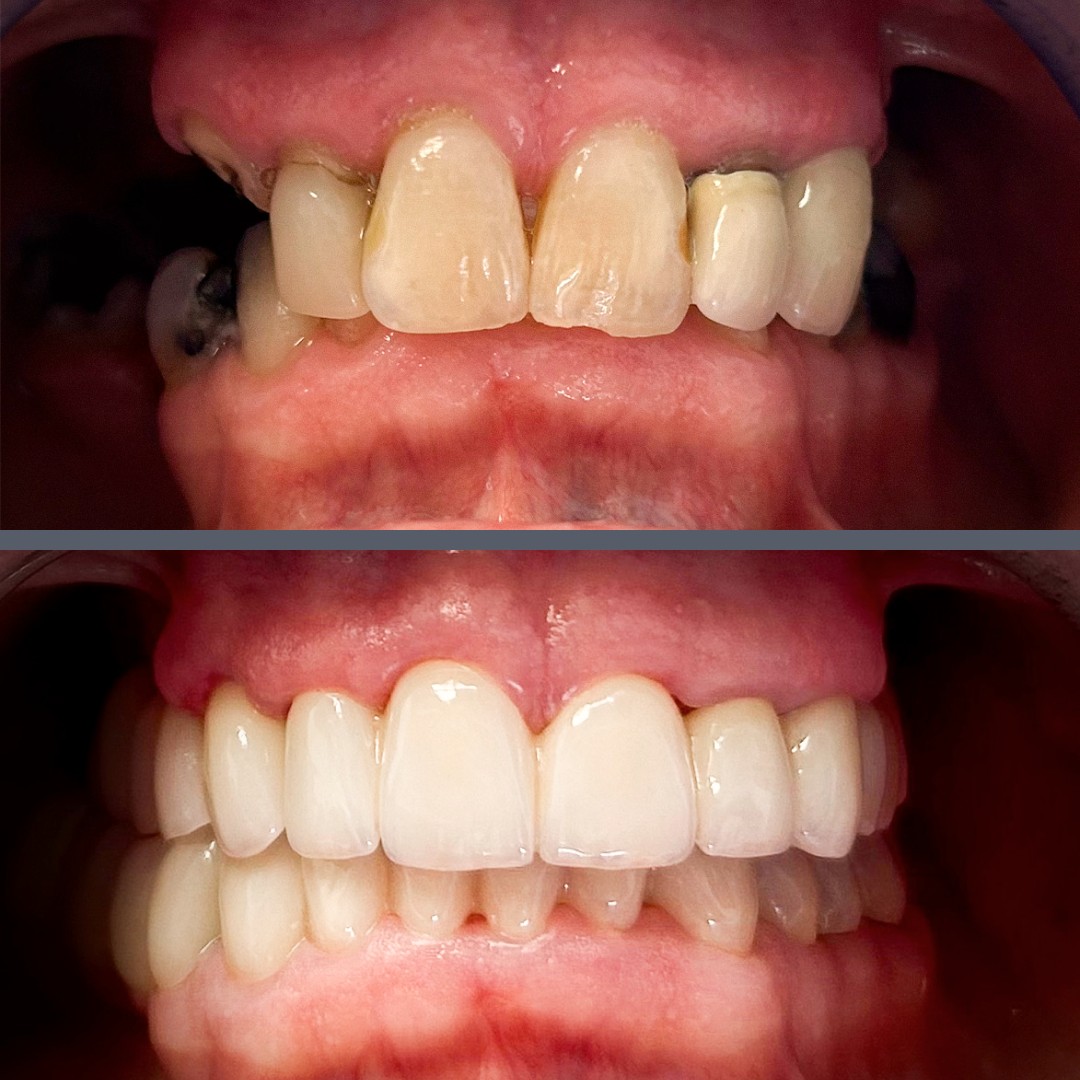

Missing Teeth and Aesthetic Problems – Full Dental Rehabilitation with Implants and Zirconia Bridges

Our Norwegian male patient presented with multiple missing teeth. His remaining teeth, especially those at the front, were also in poor condition. These serious dental issues significantly affected the overall quality of his life.

Due to financial constraints, the patient opted for a partial implant solution. We placed two implants on each side of the upper jaw, and, after the healing period, we attached bridges to the implants to replace the missing teeth. We also replaced the removed front teeth with a bridge. On the lower jaw, after extracting the remaining unsalvageable teeth and allowing the gums to heal, we fitted a full-arch zirconia bridge. The patient wore temporary prosthetics until the final restorations could be fitted.

After completing treatment in seven months and only two trips to Budapest, our patient now enjoys a fully functional and natural-looking set of teeth. This dental rehabilitation has significantly improved his confidence, self-esteem, and overall mood.